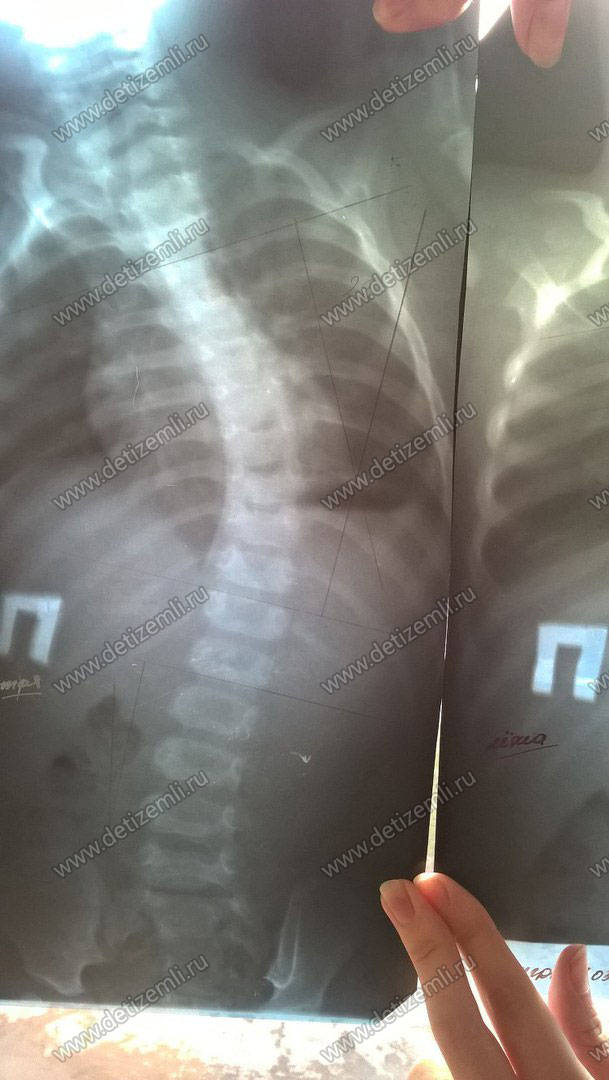

Диагноз: врожденная трехпалая кисть

Из письма мамы Макара: Я обращаюсь к вам с просьбой о помощи. В октябре 2014 г. у нас родился сынок Калашников Макар Андреевич. Но когда я увидела, что у него отсутствует левая ручка, а на правой кисти нет двух пальцев, была в шоке, ведь мы ждали здорового и полноценного малыша. Порок был выявлен только после рождения. Наш диагноз — аплазия верхней левой конечности и I–II пальцев правой кисти. Мы обратились за помощью в институт им. Альбрехта, в г. Санкт-Петербург. Нам было проведено оперативное лечение — поллицизация II пальца. Также в этой клинике было проведено протезирование нашего сыночка, которое крайне необходимо проводить ежегодно.

Сейчас ребенку срочно необходим специальный медицинский корсет стоимостью 45000 рублей. Помогите больному ребенку!

У ребенка аплазия верхней левой конечности

Калашникову Макару всего 2 года. Мальчик родился с врожденным пороком и ему срочно необходим медицинский корсет стоимостью 45000 рублей. Просим оказать помощь больному ребенку!